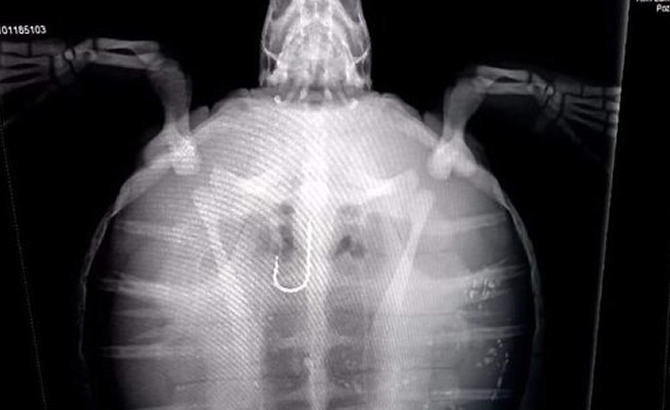

Misina ile birlikte olta iğnesi yuttuğu tespit edilen ve Berrak adı verilen henüz 3 kg ağırlığındaki kaplumbağa gözlem altında tutuluyor.